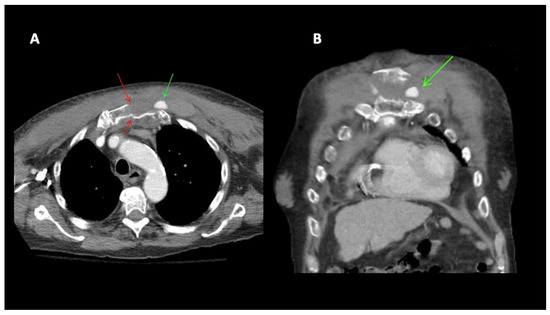

A 79-year-old male was admitted to the hospital with chest pain following a GLF. In the emergency department (ED), clinical evaluation and CT imaging revealed a sternal fracture, retrosternal hemorrhage, right pleural effusion, and left parasternal contrast extravasation. Interventional radiology was consulted, and percutaneous intervention demonstrated that a pseudoaneurysm, measuring approximately 16 mm in size, was located caudad to the clavicular head arising from a left internal mammary artery side branch (Figure 3). The patient underwent successful coil embolization, and post-procedure angiograms confirmed the effective occlusion of the left internal mammary artery, with no further visualization of the pseudoaneurysm (Figure 4). A final left subclavian control angiogram demonstrated the absence of any collateral filling of the pseudoaneurysm. Despite the successful treatment of the aneurysm, severe hepatic encephalopathy due to chronic alcoholic liver disease severely complicated recovery. Following extensive medical care, a decision was made to transition the patient to hospice care.

Figure 3. (A) 79M. Fall. CT chest with contrast. Sternal fracture (red arrows). Left parasternal active extravasation of contrast/pseudoaneurysm (green arrow). (B) Chest CT. Coronal reconstruction. Left parasternal active extravasation of contrast (green arrow).